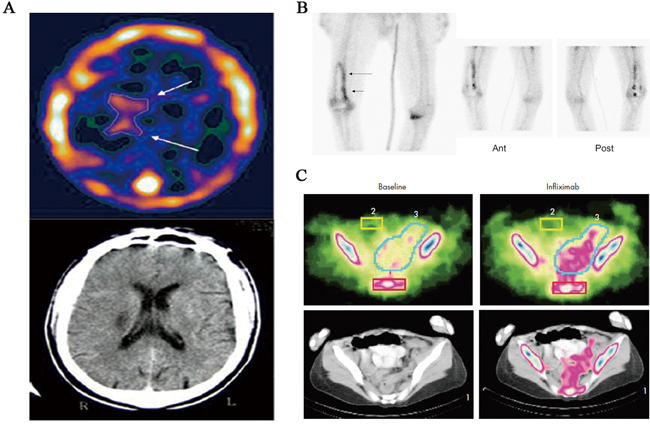

In addition, as shown in Table 3, 99mTc-Annexin V radiopharmaceuticals have also been used to image patients with diseases such as infection of prostheses, Crohn’s disease, glaucoma [38-40]. Preliminary clinical data in these patients demonstrated the clinical use of 99mTc-Annexin V as a diagnostic biomarker for monitoring apoptosis (Figure 2).

Figure 2: 99mTc-Annexin V SPECT imaging in patients with stroke, infection of prostheses, and Crohn’s disease. A. 99mTc-Annexin V brain SPECT imaging of a patient with a right peri-ventricular stroke, showing a wider distribution of Annexin V (top, arrows) compared to the CT findings (bottom). B. 99mTc-Annexin V SPECT imaging of unilateral right knee prosthesis and signs of loosening on plain radiograph. Linear increased activity around prosthesis on bone scan (planar image far left; arrows) is demonstrated, with similar activity noted on anterior (Ant) and posterior (Post) views of Annexin V study (planar images; center and right). C. Example of 99mTc-Annexin V SPECT imaging of human Crohn’s disease. Apoptosis in the intestine of patients with Crohn’s disease was visualised just before (baseline) and 24 h after infliximab treatment. The scintigraphic signals obtained corresponded with the diseased regions in the colon, indicating a correlation with disease localisation and increased 99mTc-Annexin V uptake.